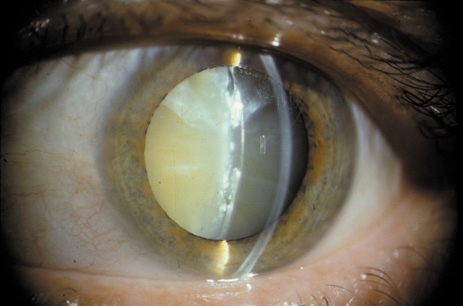

ADVANCED CATARACTS

Advanced cataracts are usually mixed cataracts that reach the mature stage. A cataract is termed “mature” if the cortex and nucleus are so opaque that one can no longer see the red reflex; at this stage the lens looks white (hence the appellation “waterfall” or “cataract”)2 (see Fig. 1). In even more advanced cases, the white cortex becomes so liquefied that one can see the outline of the brown nucleus floating free inside the lens, which usually settles down with gravity when the patient rests for a while. This is called a morgagnian cataract (Fig. 22). If the lens is noticeably swollen, the cataract is called an intumescent cataract. If the lens appears silvery white and desiccated, with some leakage of the cortical fluid, it is called a hypermature cataract (Fig. 23). As mentioned above, these advanced stages are now rarely seen in the United States but are still fairly common in less-developed countries where surgical treatment is not readily available.

Fig. 22. Morgagnian cataract. This is a mature cataract that is also intumescent (swollen), being filled with liquefied cortex. A free-floating nucleus can be seen at the bottom of the lens.

Fig. 23. Trauma-induced hypermature cataract, showing changes in the capsule. The hole seen at the 9 o'clock position was caused by penetration with a foreign body that perforated both the iris and the lens.